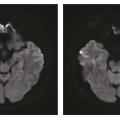

Les maladies de la mémoire peuvent être classées en deux groupes : celles qui donnent une amnésie transitoire, généralement très brève (voir le focus « Amnésies transitoires », page 1085) et celles qui engendrent une amnésie plus durable. Sont décrites ici les plus fréquentes de ces dernières.

Les amnésies transitoires occupent une place particulière dans le domaine des troubles de la mémoire. L’ictus amnésique (IA) en est le prototype,1 mais les amnésies épileptiques, vasculaires, toxiques ou traumatiques doivent aussi être prises en considération.